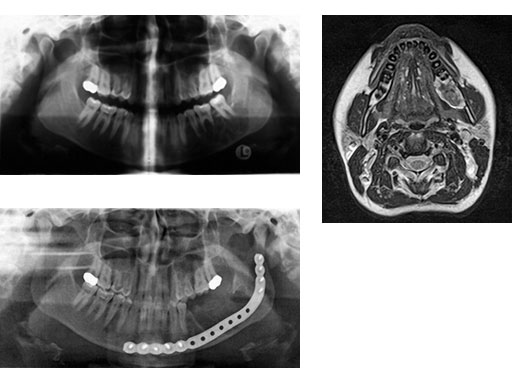

Case 1: A 27-year-old woman with an odontogenic myxoma in the left mandible. The preformed reconstruction plate was inserted prior to the tumor resection using a transoral approach with only a small additional transbuccal incision. To date the patient is free of symptoms with no signs of hypoaesthesia of the mandible and no signs of relapse. After another relapse-free period dental implants are planned for oral rehabilitation.

Fig 2

ab Preoperative radiograph and MRI.

c Postoperative radiograph.